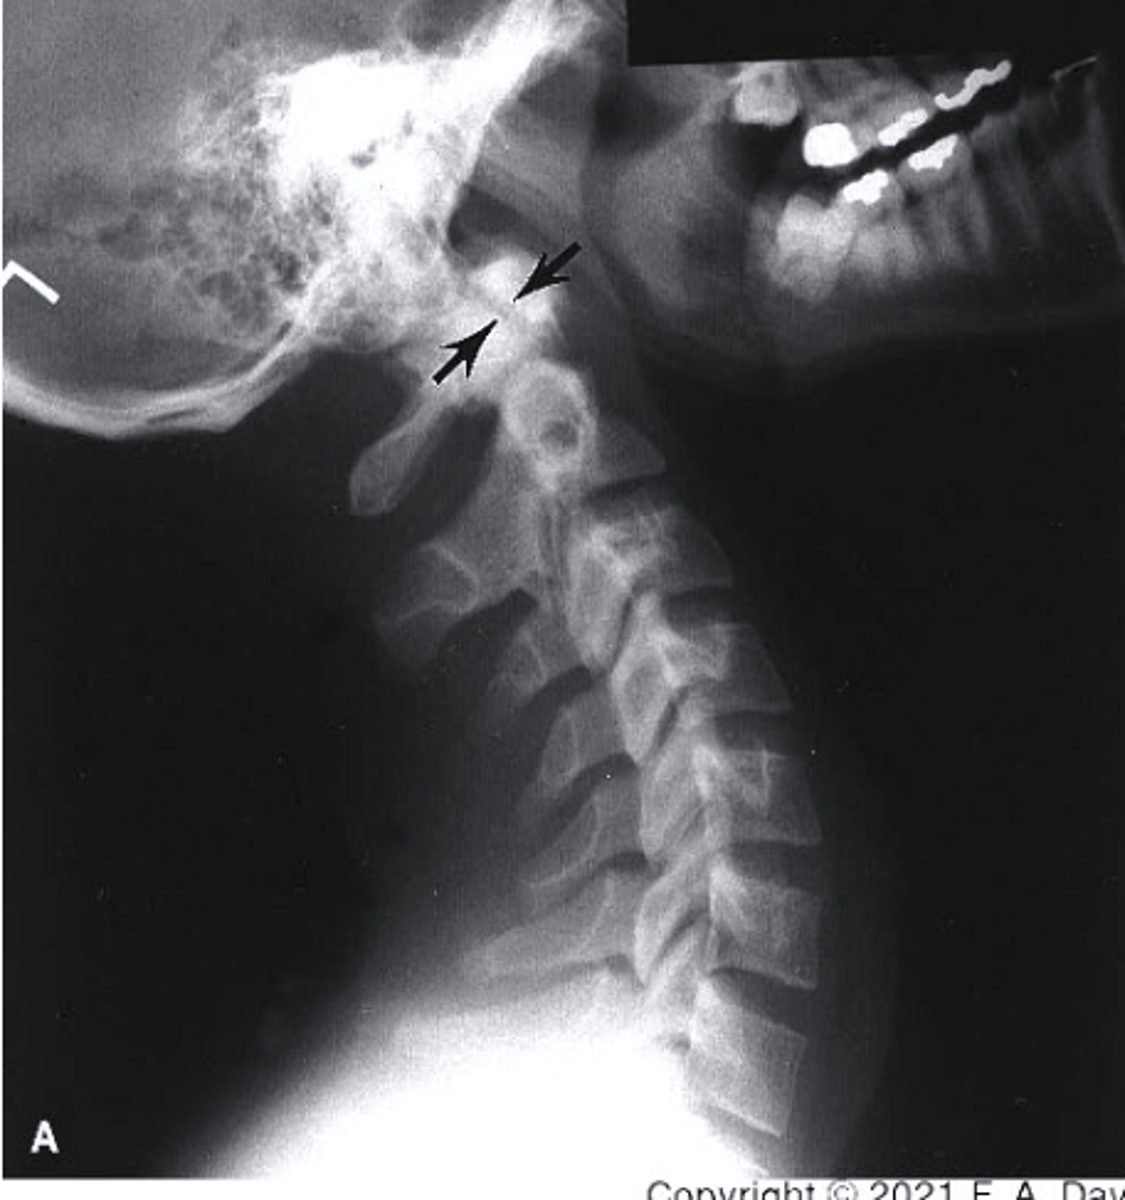

D

which structure corresponds with the retropharyngeal space?

a. Line 1

b. D

c. Line 3

d. E

E

which structure corresponds with the retrotracheal space?

Between Line 2 and Line 3

Where would the spinal cord run in this image?

a. Between line 1 and Line 2

b. Between Line 3 and Line 1

c. Between Line 1 and the soft tissue

d. Between Line 2 and Line 3